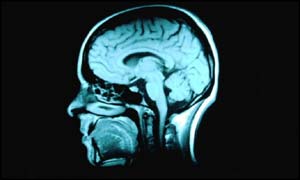

The patients had different types of brain damage

A study of more than 100 patients found distinctive brain patterns and clinical symptoms in people who have been diagnosed with the disease.

Dr Bruce Turetsky and colleagues at the University of Pennsylvania compared symptoms and brain patterns in 116 people with the disease and 129 healthy people.

They also underwent scans to examine the physical make-up and chemistry of their brain.

The tests revealed three distinct types of schizophrenia.

In the first group, parts of the brain called temporal lobes were smaller. They also transmitted fewer chemicals in these areas, which are linked to language and memory.

They had problems paying attention, organising their thoughts and expressing ideas in a logical and coherent way.

They were mostly young males who had been diagnosed with schizophrenia at an early age. It affected almost one in five of those with the disease involved in the study.

In the second group, doctors discovered changes in the frontal-striatal region of the brain. They had less grey matter in the frontal lobes and had enlarged ventricles. This area affects cognition and motor function. Their temporal lobes were normal.

Almost one in three of those with the disease who were involved in the study fitted into this category.

More than half of the remaining patients had mild memory problems. Damage to their temporal lobes or frontal lobes was not as great as those included in the other two groups.